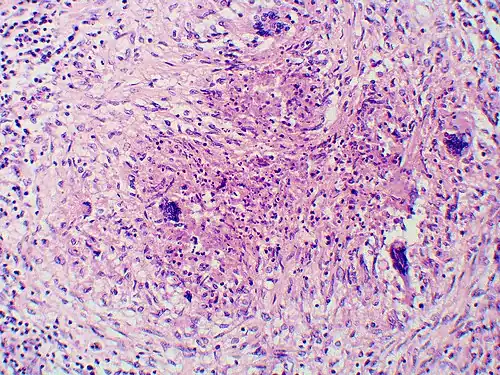

Granuloma with early suppuration. The fungal organisms are difficult to recognize at this low magnification. -

Once suspected, the diagnosis of blastomycosis can usually be confirmed by demonstration of the characteristic broad-based budding organisms in sputum or tissues by KOH prep, cytology, or histology.[27] Tissue biopsy of the skin or other organs may be required to diagnose extra-pulmonary disease. Blastomycosis is histologically associated with granulomatous nodules.